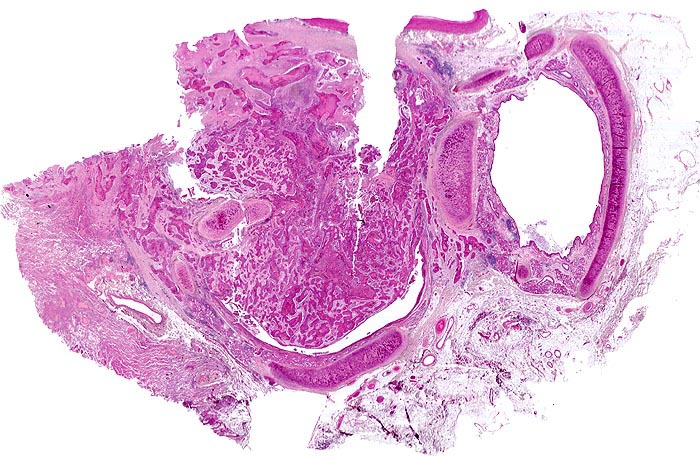

Eine Bronchuslichtung von einem Tumorzapfen weitgehend verschlossen. Rechts davon ein tumorfreier Bronchusquerschnitt. Das Tumorgewebe bildet solide Zellstränge, welche eingebettet sind in ein desmoplastisches Stroma. Zusammengequetschtes Lungengewebe am Rand der Probe.

Zentrales Bronchuskarzinom des rechten Lungenoberlappens von 5cm Durchmesser. Lungenoberlappenresektion.

Das Präparat zeigt den tumorbefallenen Bronchusresektionsrand. Die Resektion erfolgte also nicht im Gesunden.